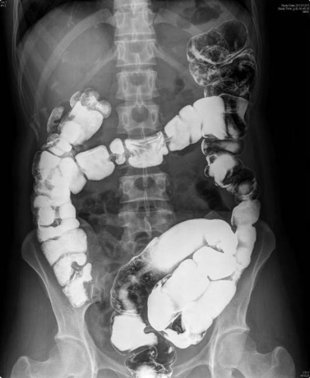

四十歲的林女士,從出生就飽受便秘困擾,且年紀愈大症狀愈嚴重,瀉藥愈吃愈多,最近就醫檢查,才發現她的腸子天生異於常人,不僅比一般人曲折,而且也比一般人要長,醫師以手術將腸道截彎取直,切除彎曲多餘的乙狀結腸50公分 ,還林女士「順暢」人生。

台中慈濟醫院大腸直腸科邱建銘主任指出,患者的腸子彎的一塌糊塗,大腸掉到直腸和子宮中間的凹陷處,已經快到肛門口的地方,九彎十八拐的路線,造成部分乙狀結腸迂迴曲折,糞便不容易通過,導致便秘。

邱主任表示,大腸直腸是消化道的末端,廣義的大腸包括結腸和直腸末端,長約120公分 到140公分 ,女性的骨盆腔較大,腸子如果又過長,就容易便秘。

邱建銘主任施以手術,切除彎曲多餘的乙狀結腸50公分 ,將腸道拉直。